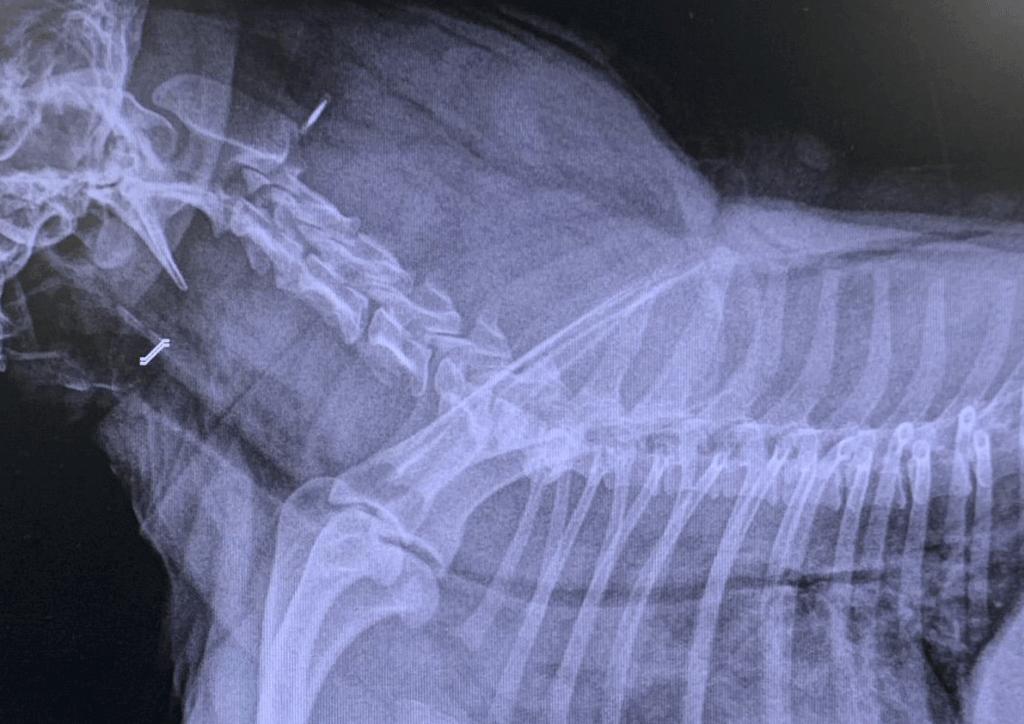

Colapso traqueal

¿Te sigues preguntando por qué tu perro tose como si tuviera algo en la garganta? Si es así, debes saber que el colapso traqueal es otra de las posibles causas que pueden producir tos en esta especie. En los perros que sufren colapso traqueal, se produce una degeneración progresiva e irreversible de la tráquea (primero de la membrana dorsal y, posteriormente, de los anillos traqueales), de manera que los anillos se van haciendo cada vez más planos, hasta que la luz de la tráquea colapsa por completo.

Los perros afectados (generalmente de razas pequeñas, edad media-avanzada y con sobrepeso) presentan como signo clínico más característico una tos seca y áspera que suena como una oca graznando, de ahí que los cuidadores suelan pensar que el animal tiene algo en la garganta. Además, estos perros suelen presentar un ruido sibilante al respirar (en forma de pitido) y otros signos como dificultad para respirar e intolerancia al ejercicio.

Esta patología ocasiona un importante perjuicio para el bienestar del animal, puesto que impide que respire con normalidad. Por ello, tan pronto como se detecte alguno de los signos que caracterizan al colapso traqueal, se debe acudir a un centro veterinario para iniciar un protocolo diagnóstico e instaurar la terapia más apropiada.

El tratamiento se puede abordar desde una perspectiva médica (con antiinflamatorios, broncodilatadores, antitusígenos, corticoides y un buen manejo dietético que favorezca la pérdida de peso) o desde una perspectiva quirúrgica (con colocación de prótesis dentro o fuera de la luz de la tráquea, u otras técnicas quirúrgicas).